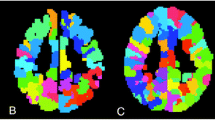

ICA is a widely utilized methodology in pediatric rs-fMRI analysis. It stands out as a data-driven approach, meaning it doesn’t rely on predefined models or assumptions about the brain’s functional networks. Instead, ICA analyzes raw rs-fMRI data, aiming to identify patterns of activity that naturally emerge. The primary goal of ICA is to find spatially independent networks within the brain [49, 51] (Fig. 1). Spatial independence implies that the identified networks are not influenced by each other; they represent distinct patterns of activity. In simpler terms, it’s akin to isolating the sound of individual instruments in a symphony that play independently.

Resting-state networks were derived using ICA analysis applied to resting-state fMRI images from two distinct groups: a cohort of adults and a cohort of premature infants. Adult ICA networks, integrated within the CONN toolbox, were derived by applying ICA to a dataset comprising 497 subjects from the Human Connectome Project database. Conversely, the resting-state networks of premature infants were obtained by applying ICA to resting-state fMRI data collected from 8 premature infants around term equivalent age

ICA focuses on detecting regions of the brain that exhibit synchronized activity. This synchronization indicates that certain brain areas are activated together, suggesting a functional connection between them. What makes ICA particularly powerful is its ability to explore various levels of brain organization, from broad functional systems to more focused, task-specific networks. A prominent example is the default mode network (DMN), which is active during periods of rest or mind wandering [52]. This network is involved in self-referential processing, autobiographical memory, and internal thought processes. The salience network (SN) acts as a filter, detecting and responding to salient stimuli in the environment. It is involved in attention, arousal, and emotion regulation [53]. The executive control network is engaged in goal-directed cognitive tasks that require planning, decision-making, and working memory [54]. It is located in the prefrontal cortex, parietal cortex, and cingulate cortex. Other important networks include the auditory network, medial visual network, lateral visual network, sensorimotor cortex, dorsal visual stream (frontoparietal attention network), basal ganglia, limbic network, and precuneus network [20, 55].

In essence, ICA serves as a detective tool for neuroscientists. It sifts through the complex data generated by rs-fMRI scans, identifies unique patterns of synchronized brain activity, and reveals spatially independent networks. Its ability to work without preconceived notions is particularly valuable in understanding the pediatric brain development, shedding light on both large and small-scale functional networks.